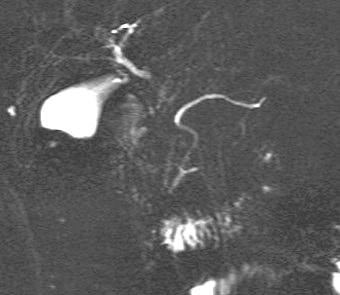

La cholangio-Wirsungo-IRM c.est

techniques ERCP ou echoendoscopie . Sur T2 les

canaux se presente de fortement hypersignal hydrique

. Le canal principale est toujour en voyant , sa

calibre est moins de 3mm de diametre avec paroi regulier . Le

canal de Santorini est en visualise non frequemment

. Le canal choledoque apparait bien limite en forme

de tube ronde de hypersignal hydrique T2 |

Image radiologique normal du

canal de Wirsung . Canal de Santorini se en voyait

fine au dessus du tier inferieure du canal de

Wirsung . . La vesicule biliaire , voie biliaire

principale est en visible tres nette .. Image des

canaux pancreatiques la vesicule biliaire et des

voies biliaires receillir par technique CPRM |